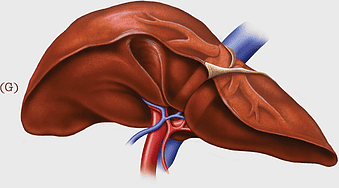

human liver anatomy, medical imaging liver, liver radiology scan, human digestive system liver, abdominal organ visualization, internal anatomy illustration, liver health diagram -

human liver anatomy, liver disease symptoms, bile production process, liver function tests, digestive health illustration, organ detoxification, gastrointestinal health benefits -

liver with gallbladder diagram, human liver function, bile production organ illustration, digestive system anatomy, liver and bile duct visual, human anatomy medical graphic, hepatology reference image -